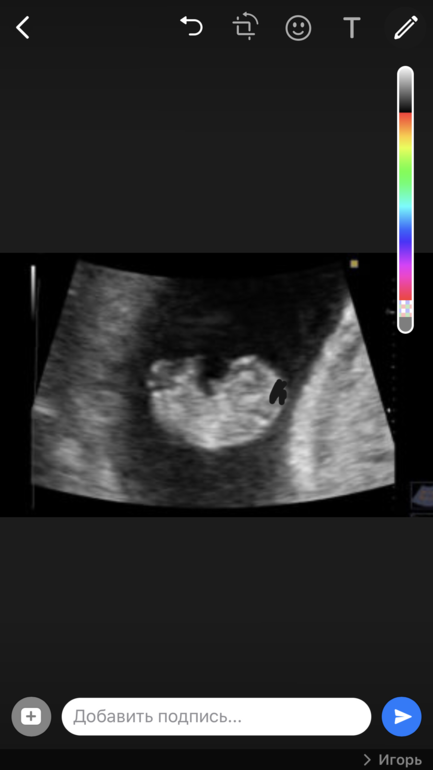

Плюс на узи, у эмбриона, в районе затылка,какое то чёрное пятно. Лично видела. Поэтому меня оставили ,что бы посмотрели другие врачи. Она толком и не объяснила, то ли много жидкости. Кто то с таким сталкивался?

Сейчас почти 9недель, о заметах ничего не сказала. Только размер эмбриона, 22 мм. Я так понимаю это может быть гидроцефалия?